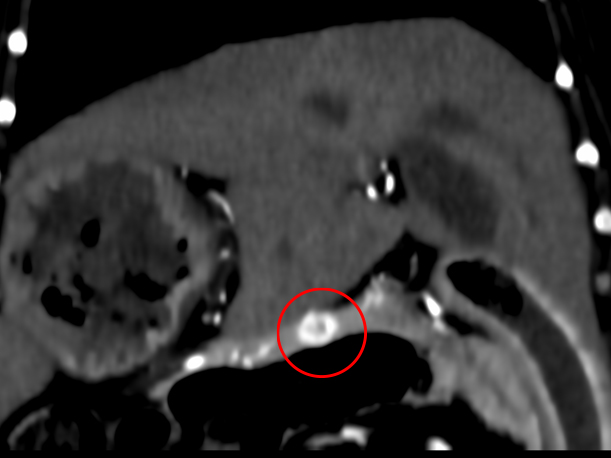

症状は特に見られなかったものの、血液検査で血糖値が低いことがわかりました。また、その時に測定したインスリンの値が高くなっていたため、膵臓に問題があるのではないかと考えました。 超音波検査を行いましたが、膵臓の位置の関係で腫瘤(しゅりゅう:できもの)をはっきり確認することが難しかったため、CT検査を実施したところ、膵臓の一部に腫瘤が見つかりました。 この結果から「インスリノーマ」という膵臓の腫瘍が強く疑われたため、腹腔鏡(ふくくうきょう)という小さな傷で体への負担が少ない手術で、腫瘤の摘出を行いました。 手術後の経過はとても良好で、術後3日で元気に退院されました。

術前のCT検査 CT検査にて腫瘤の位置、転移の有無を確認